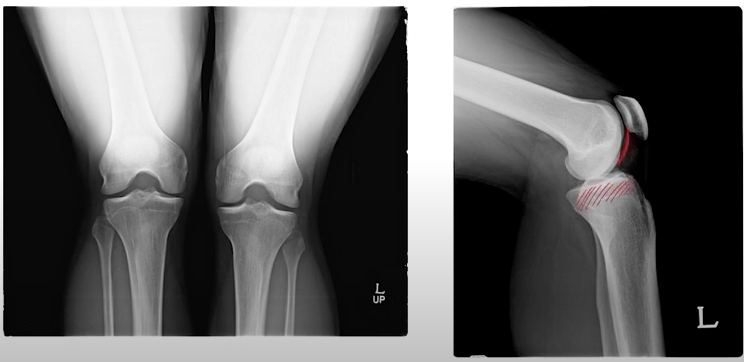

탁자위에 구슬이 있는 경우 자유로운 움직임은 좋지만, 오래 사용하게 되면 어떻게 될까요?

일자인 부분은 모양의 변형이 오게 될 것 이고, 대퇴골을 앞이나 뒤로 탈구하게 될 것 입니다.

이러한 불안정성을 위해 구슬과 같은 대퇴부위를 잡아주는 해부학적 구조물이 바로 "반월연골판(Meniscus)" 입니다.

탁자위에 고무타이어를 둘러서 구슬이 안빠져나오게 한다고 생각하면 쉽게 이해할 수 있습니다.